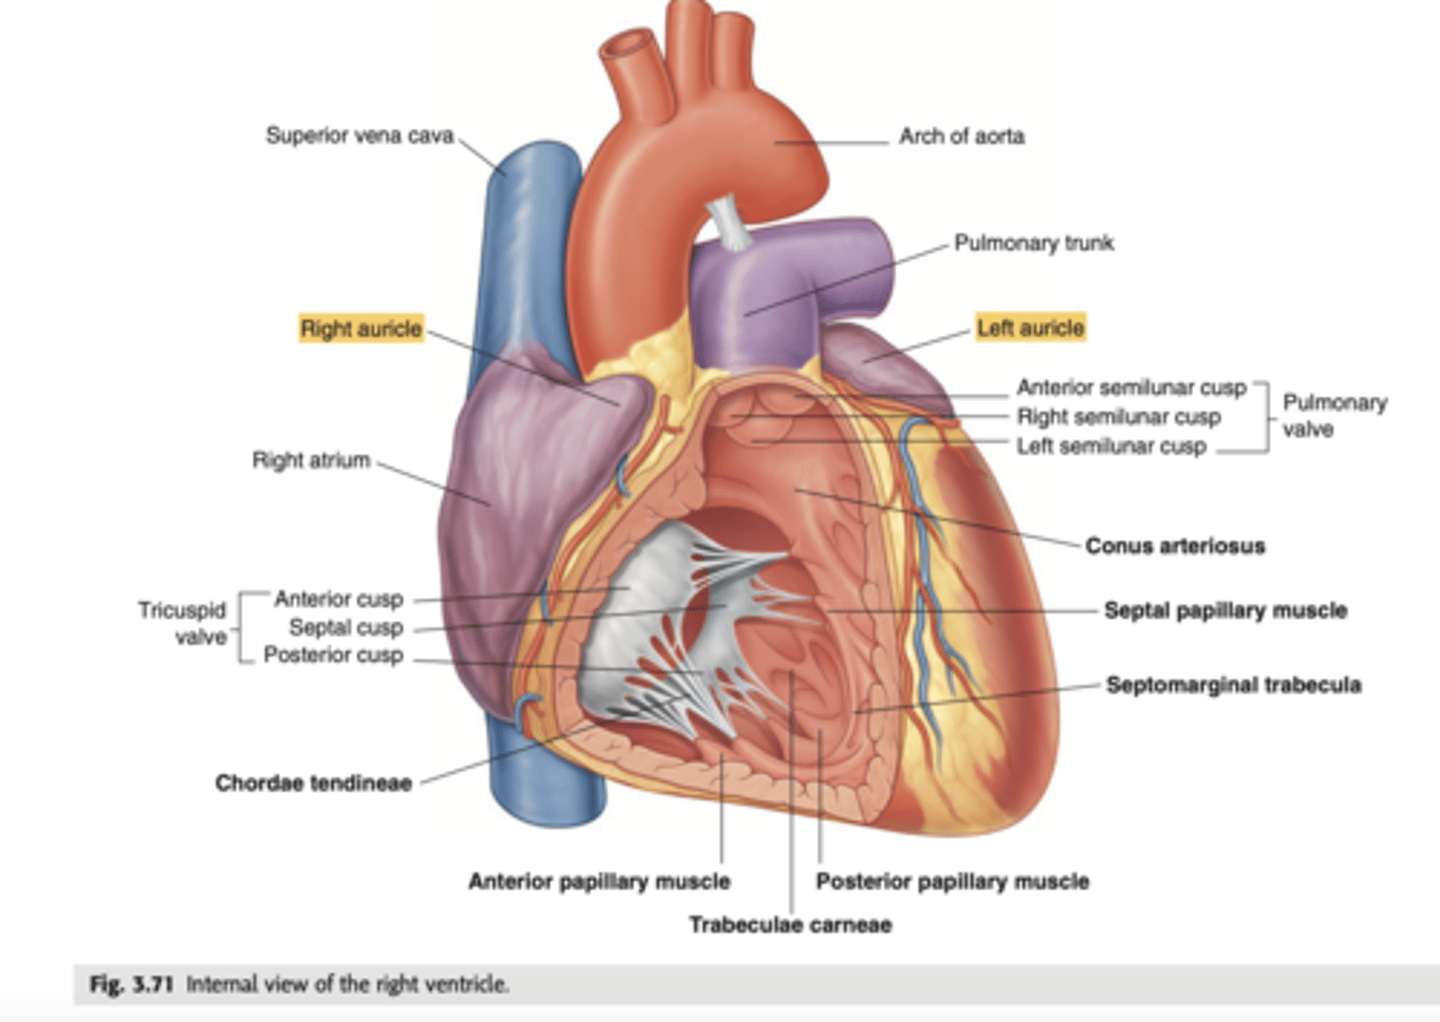

What are the walls of the right ventricle?

. Anterior wall

. Posterior wall

. Septal wall

Right ventricle has a conical shape with 2 o 3 walls

Describe the two portions of the medial/septal face/wall of the right ventricle.

infundibulum or outflow region or conus arteriosus (smooth and membranous)

trabeculae carnae (muscular and irregular)

What are the 3 cusps of the tricuspid valve?

Anterior

Posterior

Septal

What connect the cusps of the valve a to papillary muscles in the

right ventricle?

Chordae tendinae

With the contraction of the walls of the ventricle what's the action of the papillary muscles?

contract as well

With the contraction of papillary muscles what will be happen with the valve?

Close

What is the septomarginal trabeculae (or moderator band)?

Part of the conduction system of the heart.

electrical waves pass through this band to reach the papillary muscles.

LANDMARK

What are the positions of the pulmonary valve cusps?

Anterior

Right

Left

What are the 3 parts of the pulmonary valve?

. Nodules. (little point at the center)

. Lunules (from the nodule to the wall)

. Sinus (left in between)